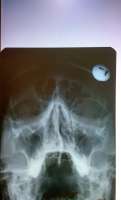

>>752738Сделал рентген, врач назначил мометазон. Сказала, ситуация как при обычном насморке. Что ещё можно сказать по снимку?